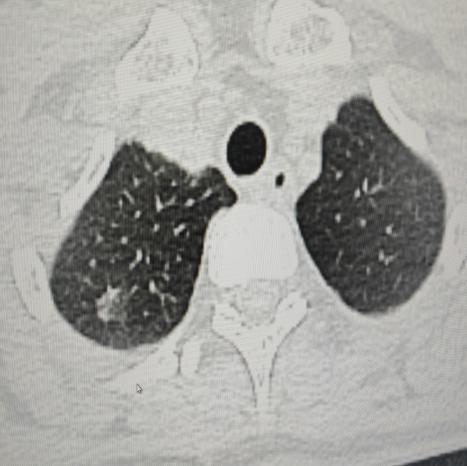

4.新疆医院顺利完成首例胸腔镜下肺叶部分切除术

5月16日,驻疆专家马震川与自治区人民医院专家合作,完成首例胸腔镜下肺叶部分切除术,彰显国家呼吸区域医疗中心在疑难重症治疗方面的技术优势。